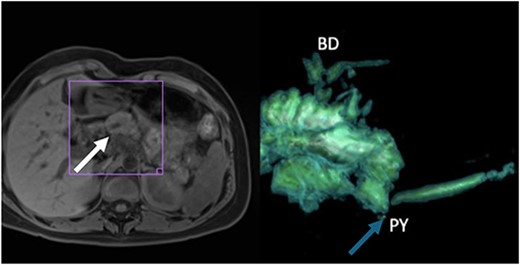

After maintaining repetitive episodes of acute pancreatitis for 3 months after the first episode, it was decided to perform a magnetic resonance cholangiography, where a 6.1-mm pancreatic duct was determined (Fig. 2), suggestive of PJ stenosis.

(A) Thickening of the tail of the pancreas with hyperintensity in diffusion sequence (white arrow), anteroposterior diameter 30 mm, inflammatory changes in the body and neck of the pancreas, discreet postcontrast enhancement, and findings suggestive of recurrent interstitial edematous acute pancreatitis; (B) 3D reconstruction with evidence of narrowing of the pancreatojejunal anastomosis (blue arrow).